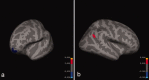

Creativity has long been a construct of interest to philosophers, psychologists and, more recently, neuroscientists. Recent efforts have focused on cognitive processes likely to be important to the manifestation of novelty and usefulness within a given social context. One such cognitive process - divergent thinking - is the process by which one extrapolates many possible answers to an initial stimulus or target data set. We sought to link well established measures of divergent thinking and creative achievement (Creative Achievement Questionnaire - CAQ) to cortical thickness in a cohort of young (23.7 +/- 4.2 years), healthy subjects. Three independent judges ranked the creative products of each subject using the consensual assessment technique (Amabile, 1982) from which a "composite creativity index" (CCI) was derived. Structural magnetic resonance imaging was obtained at 1.5 Tesla Siemens scanner. Cortical reconstruction and volumetric segmentation were performed with the FreeSurfer image analysis suite. A region within the lingual gyrus was negatively correlated with CCI; the right posterior cingulate correlated positively with the CCI. For the CAQ, lower left lateral orbitofrontal volume correlated with higher creative achievement; higher cortical thickness was related to higher scores on the CAQ in the right angular gyrus. This is the first study to link cortical thickness measures to psychometric measures of creativity. The distribution of brain regions, associated with both divergent thinking and creative achievement, suggests that cognitive control of information flow among brain areas may be critical to understanding creative cognition.